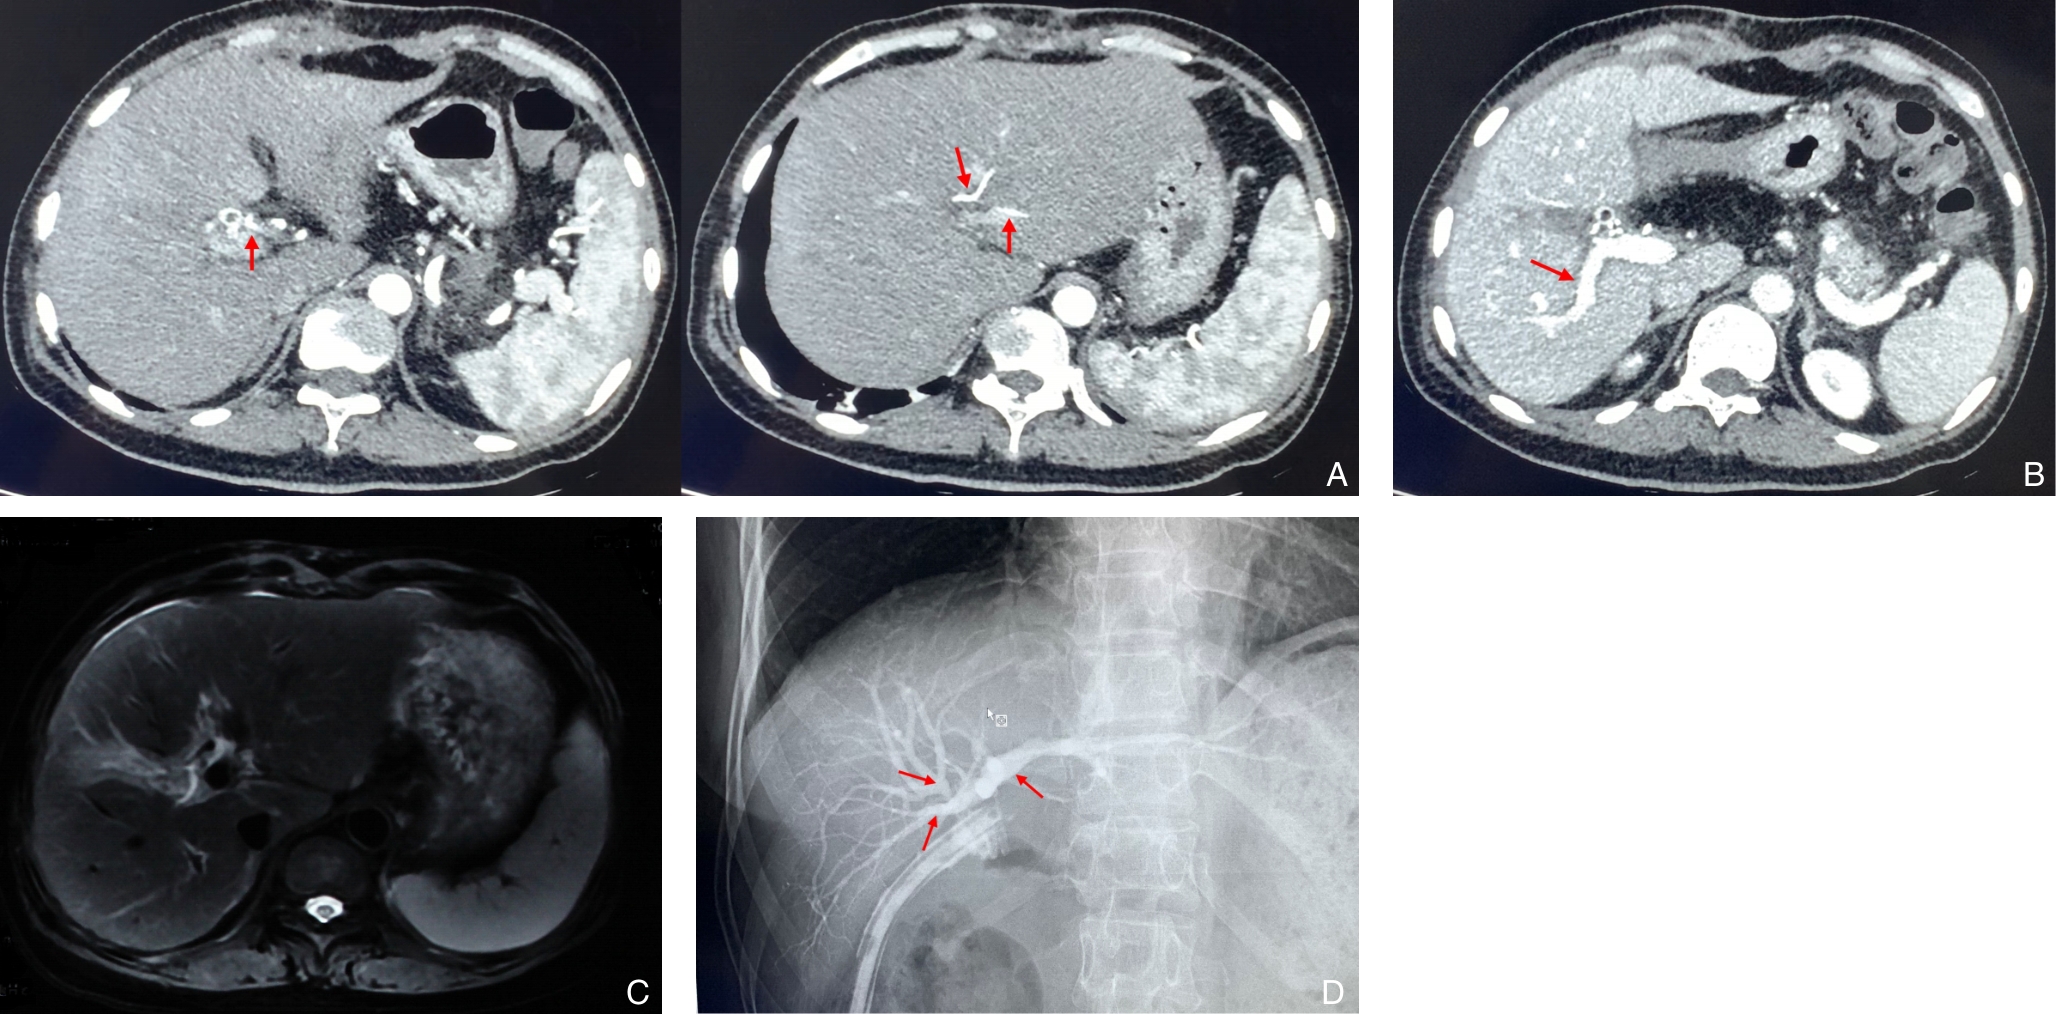

摘要:医源性胆管损伤(IBDI)是常见的胆管损伤类型,多发生于胆囊切除术。随着腹腔镜胆囊切除术的普及,其发生率明显高于开腹手术,且合并血管损伤(VI)的复杂病例逐渐增多,增加了诊治难度,严重时可导致肝缺血及萎缩。肝管空肠吻合术是胆管损伤后常用的重建方式,若合并VI,则可能需行肝切除。本文报告笔者收治的1例53岁女性患者,因胆囊切除术后出现胆汁漏入院。经2次多学科团队(MDT)讨论,术前评估显示肝右动脉及门静脉分支损伤并伴右前叶萎缩。根据术中所见,最终实施右半肝切除联合左肝管空肠Roux-en-Y吻合术。患者术后恢复顺利,随访6个月无明显不适。通过对该病例的诊治过程及文献的回顾与分析,本文总结了复杂IBDI的临床特点、诊治策略及MDT模式的价值,以期为临床实践提供借鉴。